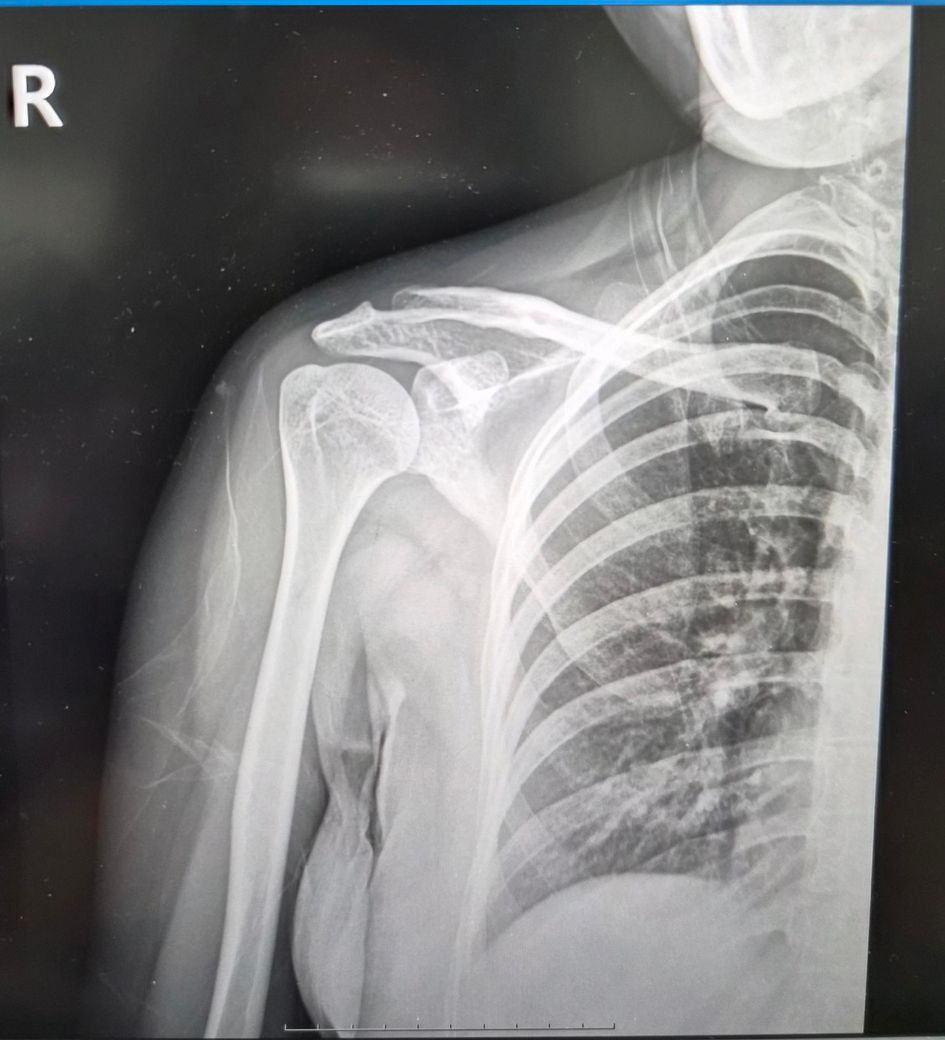

2024년도에 전동차가 전복되면서 왼쪽어께 다치면서 어께가 많이 안좋아요.

2025년10월14일 찍은 오른쪽,왼쪽어께사진이랑

2026년2월19일 목요일 오른쪽,왼쪽어께사진이랑

비교해주세요.왼쪽어께가 찌릿하고 통증있어요.

2025년도 찍은거랑 2026년 찍은거랑 차이 많이 나보이죠?

• 2번 째 사진

비교해보면 뼈의 정렬이나 관절간격,건봉모양 같은 기본부조는 크게 달라진 부분이 없어보입니다. 짧은시간사이에 관절이 급격히 닳았다거나 뼈가 무너졌거나 하는 진행성 변화는 뚜렷하지 않습니다. 다만 원래부터 견봉아래 공간이 약간 좁은 구조라서 회전근대 힘줄이 지나가는 공간이 넉넉한 편은 아니고,이런 해부학적 형태는 시간이 지나면서 염증이나 충돌증상이 반복될 가능성은 있습니다. 마지막 MRI 단면을보면 회전근개 힘줄부위에 염증또는 부분손상으로 의심되는 신호변화가 보입니다.염증,부분파열 또는 퇴행성 변화기능성이 있습니다. 이런경우 팔을 90도이상 올릴때 통증이 심해지는 양상이 흔합니다. 빠른쾌유를 빕니다!

오른쪽은 비교적 차이가 없지만 왼쪽은 살짝 차이가 있습니다.

다만 엑스레이 촬영시 자세적인 문제, 통증에 의한 근육 사용패턴 문제 등 차이가 날 수 있기에 좀 더 정확한 소견은 전문의에 판독을 들어보시길 바랍니다^^

사진만으로 보면 "2025년 대비 2026년 X-ray에서 뼈 위치가 크게 변했다거나 탈구.골절이

새로 생긴 차이는 뚜렷하지 않습니다."

다만 X-ray는 "근육.힘줄.회전근개.신경 문제를 거의 못 봅니다" 찌릿한 통증은 이런 연부조직/신경 원인이 흔해요.

전동차 전복 외상 병력이 있고 통증 지속이면 "회전근개 손상, 충돌증후군, 경추 연관통" 가능성 있습니다.

“차이가 많이 난다”기보단 "X-ray로는 한계가 있고, MRI가 꼭 필요한 상황"으로 보입니다.